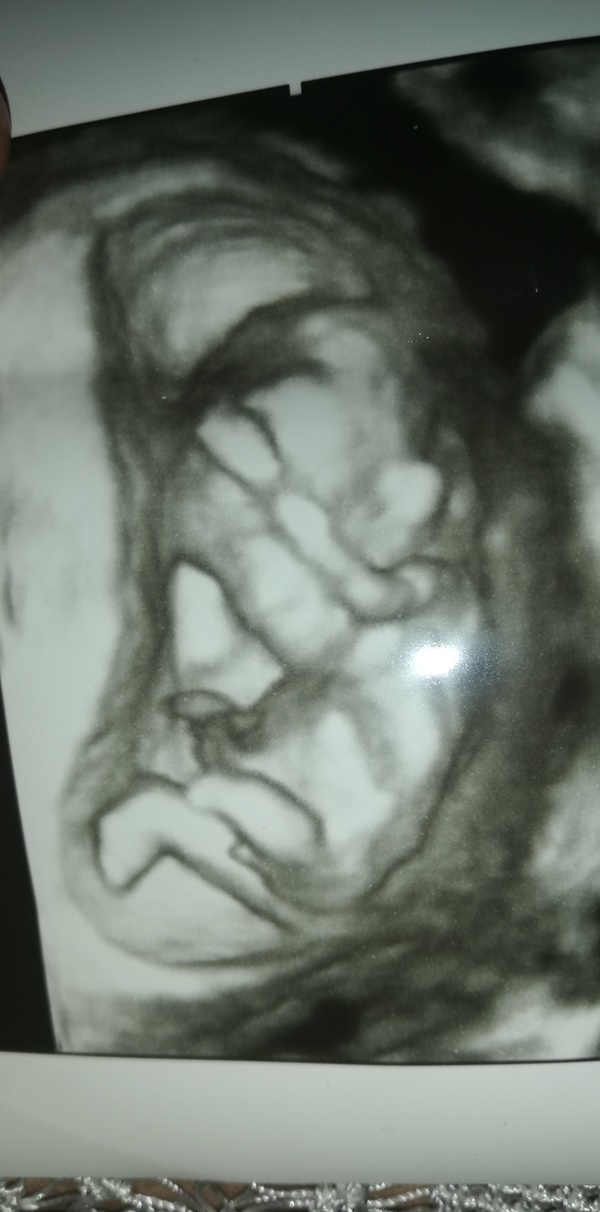

Merhabalar, ben de tahmin alabilir miyim?

"Bu haftalarda bebegin cinsel organi genital tüberkül seklindedir farklilasarak ya kiz yada erkek organina donusecek bi yapi seklindedir ve ultrasonda bu genital tüberkül bebekle olan acisina bakarak paralelse kiz yukari bakiyorsa erkek olarak ancak %90;lik bir varsayimda bulunabiliriz.

2;nci haftayi beklemek durumundasiniz 2;nci haftada arti bu genital tüberkül degil genital organ olacaktir ama bu haftalara gelene kadar anneler arasinda cesitli soylentiler ve inanislar vardir cin takvimine bakarak yada karnin sekline bakarak, yedigine ictigine bakarak veya karin bolgesine yuzuk tutarak anlamaya calisirlar. Ama dedigimiz gibi karisikligi ortadan kaldirmak adina 16nci haftadan once hicbir ultrasonografi, cihazi bebegin cinsiyetini %100 oraninda belirleyemez.